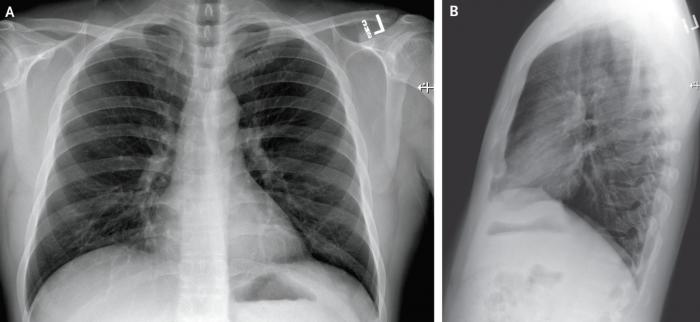

2020年1月22日(患病第7天,住院第3天)的后前胸和外侧胸片。